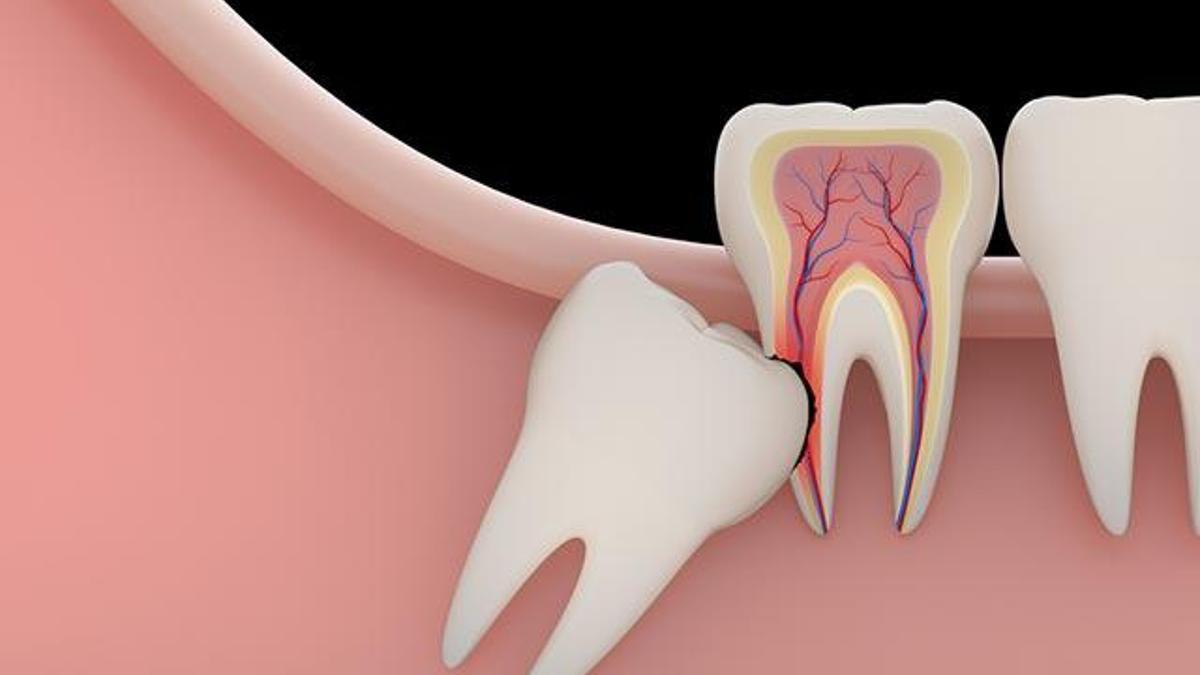

20 Lik Dis Cikarken Dis Eti Sismesi

20 Lik Dis Damak Sismesi Belirtileri Ve Tedavisi Damak Gen Tr

20 Lik Dis Hakkinda Arsivleri Sayfa 3 8 Orident 20 Lik Dis

20 Lik Disler Cenenizi Bozmasin Saglik Haberleri